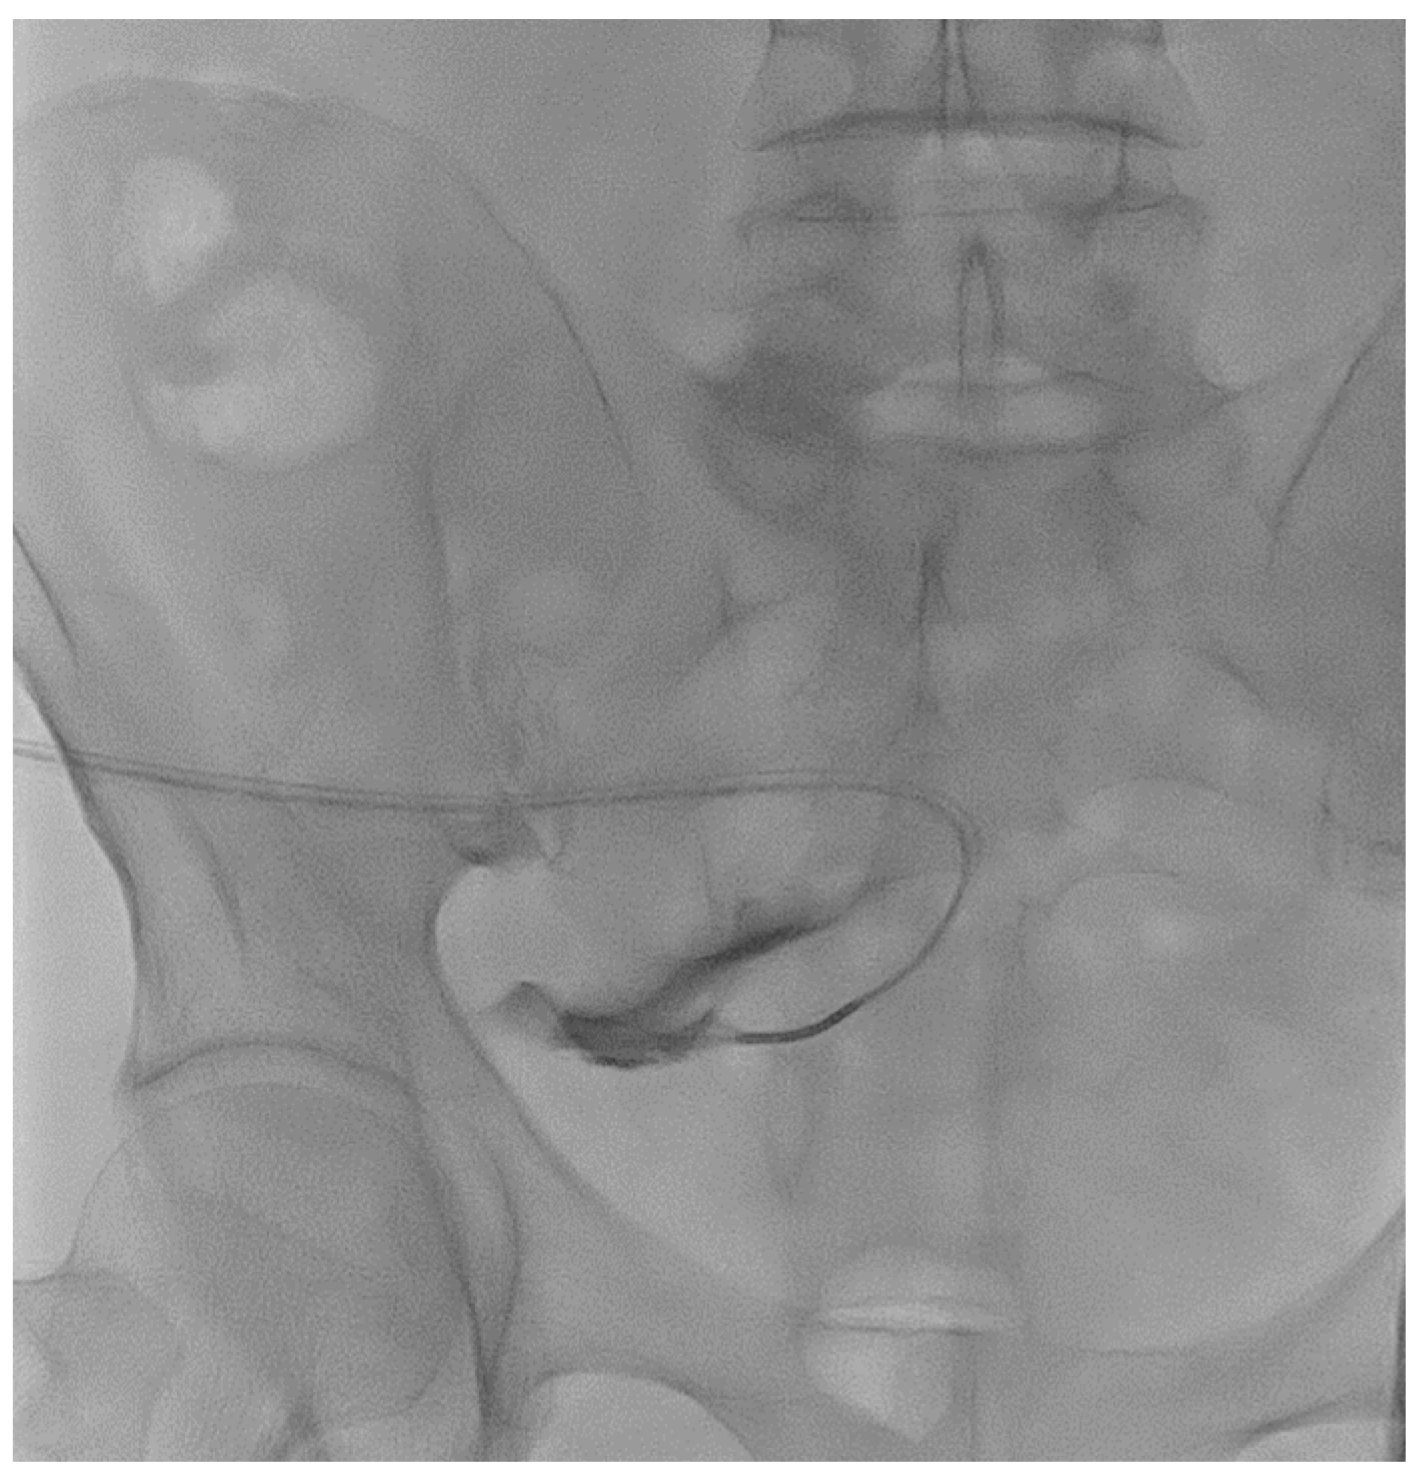

A 48-year-old male patient affected by ADPKD underwent right nephrectomy and concurrently videolaparoscopic peritoneal catheter placement. Two months later, due to persistent abdominal bulk secondary to the contralateral kidney size, the patient underwent a second surgery for left nephrectomy. Three months after the start of peritoneal dialysis, poor inflow and outflow performance was detected with little benefit from laxatives administration. An abdomen X-ray showed the peritoneal catheter rising from the lumbar left region with the tip ending in the lumbar right region (Figure 1).

The next day—after adequate antibiotic prophylaxis—the patient underwent catheterography and radiological manipulation of the catheter with repositioning of the catheter tip in the pelvis. Afterward, the patient could immediately and effectively resume peritoneal dialysis, and no complication of the procedure occurred. The peritoneal catheter was well-functioning one month after the procedure.

Figure 1. Catheterography showing the tip (Life 14 01475 i001) of the peritoneal catheter pointing to the lumbar right region. Normal spillage of the contrast medium from the side holes may be seen (Life 14 01475 i002).